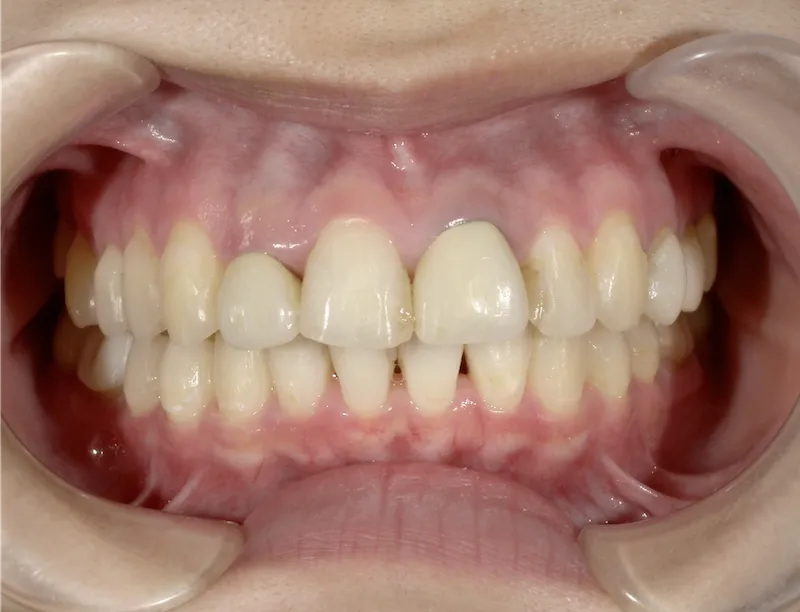

痛くない・しみないのに、45分で白くなる。

45分で白くなる。